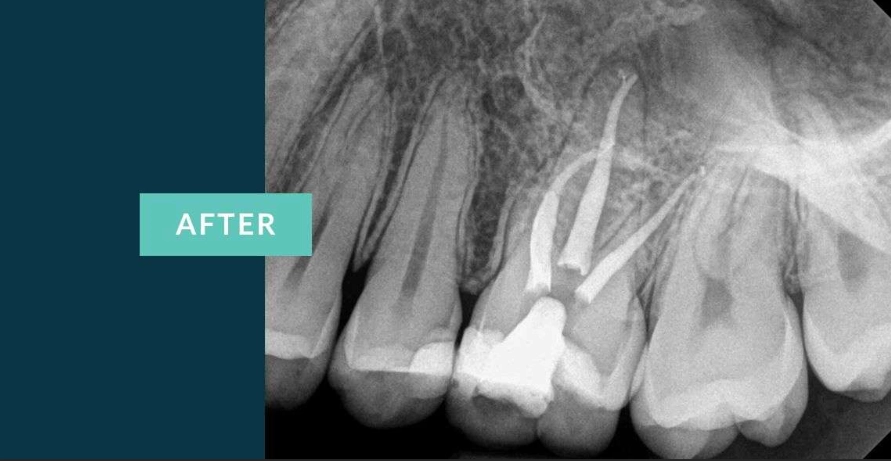

First, good imaging is non-negotiable. A periapical X-ray shows the length of the roots. For complex cases, a 3D cone beam CT scan might be used. This gives a detailed map, crucial for navigating those tricky, multi-canal premolars. Your dentist will also administer local anesthesia. The idea that root canals are painfully done is a complete myth—if you feel sharp pain, speak up. More anesthetic can be given. You should only feel pressure.

Access and Cleaning: A small opening is made in the top of the tooth. Using very fine files, the dentist removes the diseased pulp and meticulously cleans and shapes each canal. This is where the microscope is a game-changer. It allows the clinician to see intricate details, find hidden canals, and ensure no debris is left.

Disinfection and Filling: The canals are flushed with antimicrobial solutions. Once dry, they are filled with a rubber-like material called gutta-percha, sealed in place with a biocompatible cement. The goal is to hermetically seal the space to prevent re-infection.

The Temporary Fill: The access hole is closed with a temporary filling. The entire process for a premolar typically takes 60 to 90 minutes, sometimes split over two visits if there's a significant infection that needs time to drain.